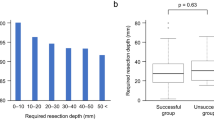

Table 2 shows the stain-lesion distances and successful localization rates by location and pathological diagnosis. There was no significant difference in stain-lesion distance between left and right lungs. The stain-lesion distances were not dependent on the type of histological diagnosis, lesion sizes, age and sex. The lower lobes had a significantly longer stain-lesion distance than upper and middle lobes with a crude average of 3.0 (95% CI: 1.6, 4.3) mm (p<0.001). Further controlling for age, sex, lesion size and pathological diagnosis using the multiple linear regression method, the adjusted difference between lower and upper/middle lobes in stain-lesion distance remained statistically significant with a mean of 3.0 (95% CI: 1.7, 4.4), p<0.001. However, about 80% stain-lesion distances were<5 mm for lesions on middle/upper lobes while 80% stain-lesion distances were <10 mm for lesions on the lower lobes (Figure 7). The successful localization rate was 98% (95% CI: 90, 100) for lesions in upper or middle lobes, which was significantly higher than that for lesions in lower lobes (86%), p=0.036. There were no significant differences in the successful localization rate or stain-lesion difference between left and right lungs and between benign and malignant lesions.